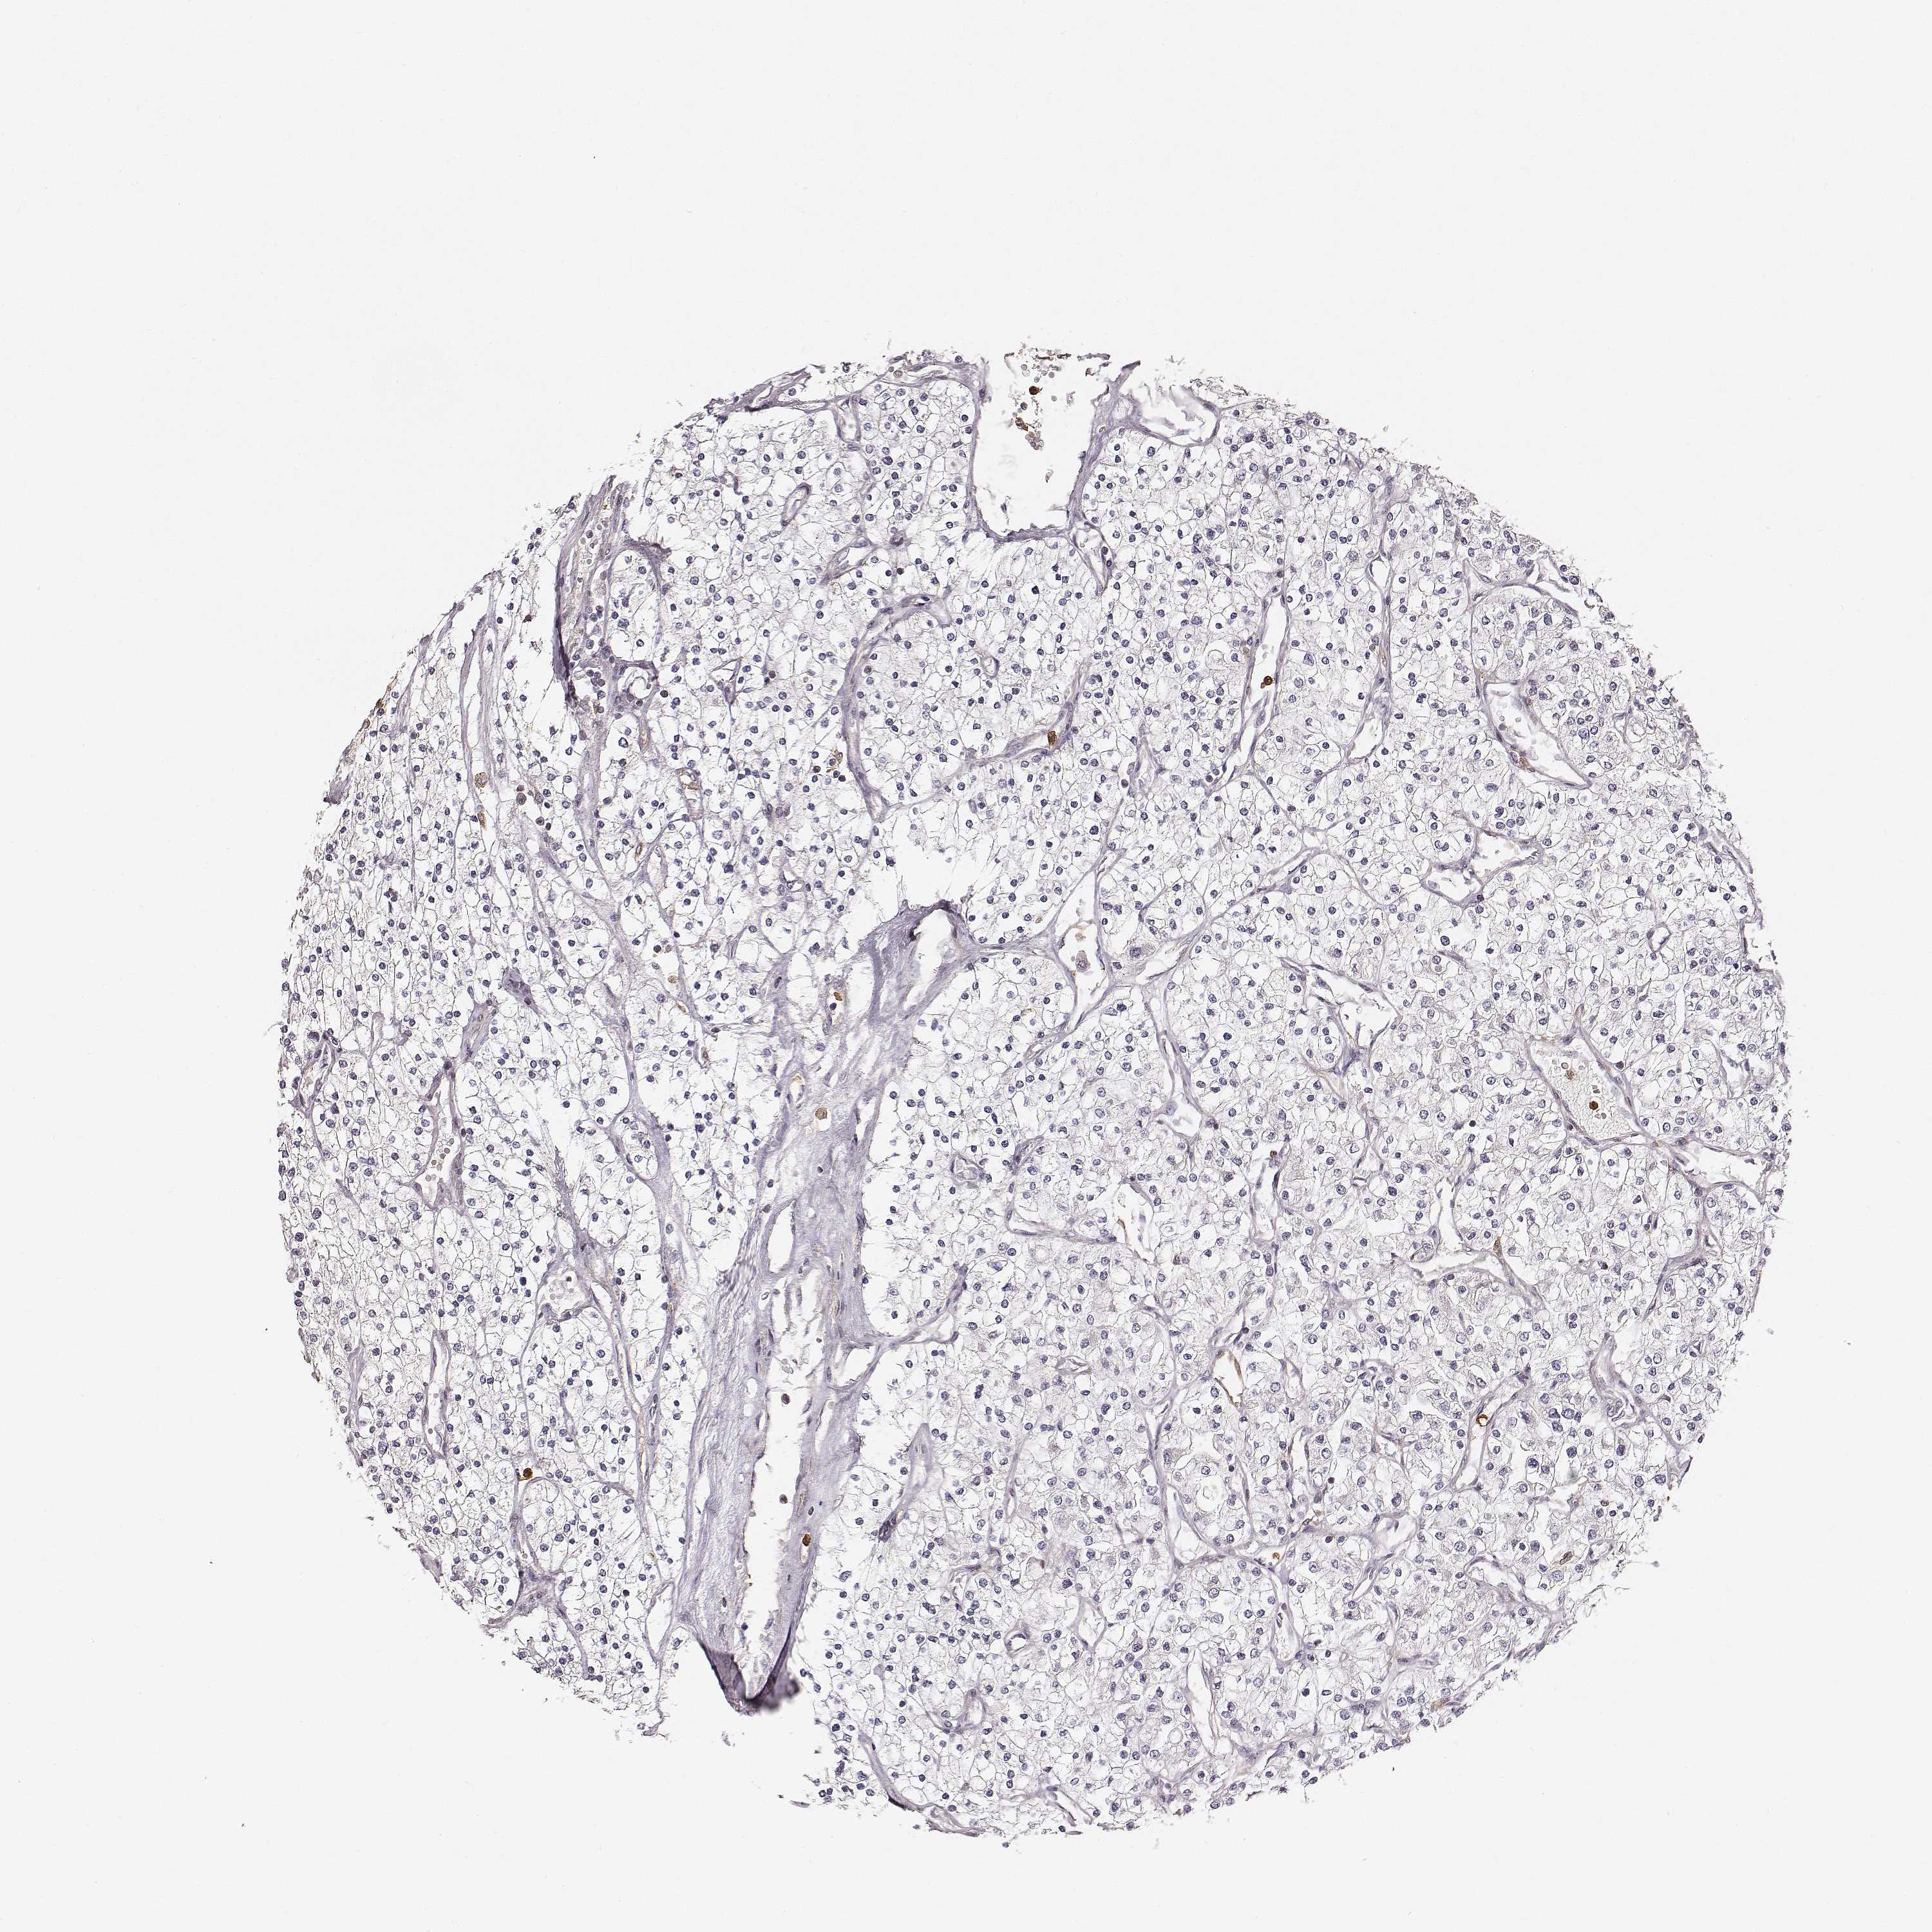

KIDNEY RENAL CLEAR CELL CARCINOMA (VALIDATION) - Interactive survival scatter ploti

ZYX is not prognostic in Kidney Renal Clear Cell Carcinoma (validation)

: 43

Average pTPM 59.2

Number of samples 100